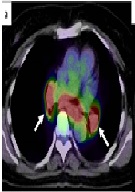

Sarcoidosis as Hepatic, Splenic, and Para-aortic Lymph Nodules, Mimicking Colon Cancer Metastases: A Case Report

Kenichi Maeda, Nobuhisa Matsuhashi*, Takao Takahashi, Tomonari Suetsugu, Yoshinori Iwata, Takeharu Imai, Toshiyuki Tanahashi, Satoshi Matsui, Hisashi Imai, Yoshihiro Tanaka, Kazuya Yamaguchi, Shinji Osada, Kazuhiro Yoshida